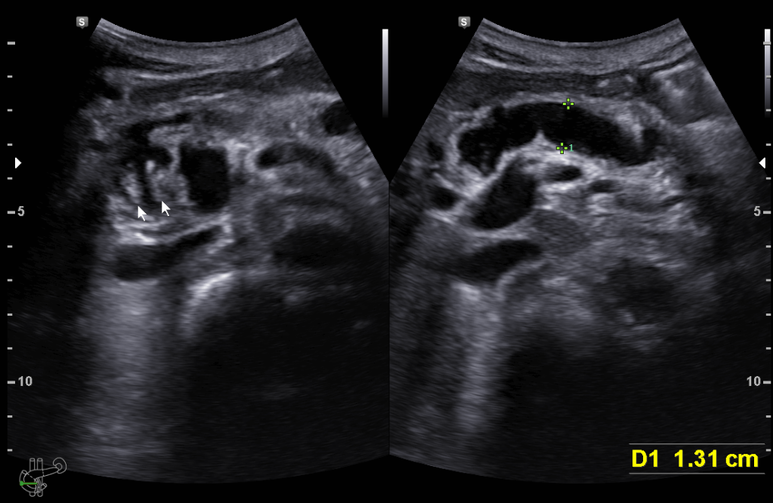

상기 환자 초음파 시행

체부 췌도가 13 mm까지 확장

미부도 확장 확인

췌두부의 췌도 확장과 결절 소견